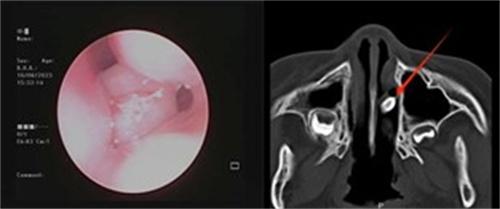

接診的李圓副主任經(jīng)過仔細(xì)檢查,發(fā)現(xiàn)小朋友出現(xiàn)鼻塞的原因,并不是普通的鼻炎導(dǎo)致的,于是做了鼻腔內(nèi)鏡的檢查,看見左鼻通道內(nèi)有粘稠的膿性鼻涕,用吸引器將鼻涕吸走之后發(fā)現(xiàn)中后段有黃豆大小的新生物,為了確定物質(zhì)的性質(zhì),李圓也讓患兒做了鼻腔內(nèi)部的CT

考慮到小朋友年齡只有5歲,在配合程度上比較低,于是李圓立刻聯(lián)系麻醉,以及手術(shù)時(shí)把手術(shù)安排在第2天早上,10多分鐘便將手術(shù)順利完成,取出鼻腔內(nèi)的異物后,發(fā)現(xiàn)是一個(gè)還帶著牙根的乳牙。